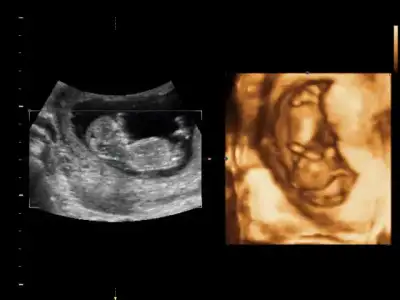

sağol canım ağzına sağlıkCanım seninkini erkek bebeğe benzettim ikinci Fotoğrafın alt kısmında bir şeyler var gibi. Ama bebek arkasını dönmüş bu teori için yandan ya da önden olması lazım Fotoğrafın.

Canım nub teorisi için 12-13 haftalar en ideal haftalar. Kese teorisine koy istersen ama bence o teori nub teorisi gibi bilimsel değil.

Tamam canım inşAllah. Ikili teste gittiğinde Bebeğin yandan fotoğrafını iste. O hafta en uygun zaman.Cevabin için tesekkur ederim canım kismet olursa 4 hafta sonra koyarım o zmn yorumlarsin insallah